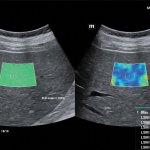

با توجه به اینکه دستگاه های جدید بررسی فیبروز کبد (سفتی کبد)بر پایه سونوگرافی میباشد،در مرکز تخصصی  فیرواسکن دکتر شماعی ،فیبرواسکن کبد صرفا توسط پزشک متخصص رادیولوژی  انجام می‌شود و علاوه بر انجام فیبرواسکن و ارزیابی فیبروز( سفتی ) کبد و تعیین میزان  کبد چرب، سونوگرافی کبد و بررسی کیسه صفرا و مجاری صفراوی نیز بدون دریافت هزینه انجام خواهد شد

مرکز تخصصی فیبرواسکن دکتر شماعی جز محدود مراکزی در مشهد میباشد که انجام فیبرو اسکن با استفاده از جدید ترین دستگاه ها انجام میگرد  و تمامی مراحل انجام فیبرواسکن و تجزیه و تحلیل اطلاعات و گزارش فیبرواسکن توسط پزشک متخصص صورت می‌گیرد.

با توجه به اینکه نتایج فیبرواسکن کبد نقش تعیین کننده در درمان کبد چرب دارد،لذا این مرکز متعهد به انجام فیبرواسکن کبد توسط پزشک متخصص و با صرف وقت لازم میباشد